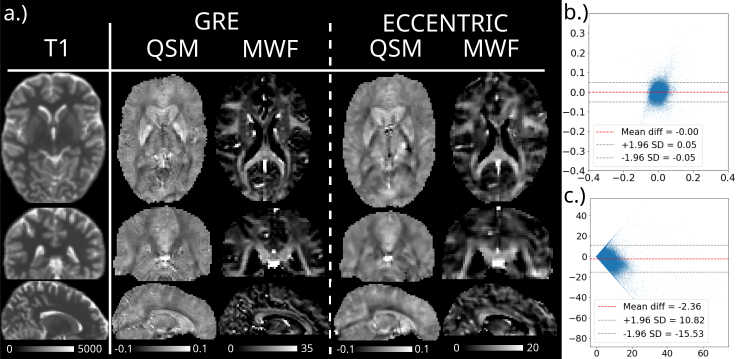

Figures 7 and 8 show a comparison of QSM and MWF in one healthy volunteer (Fig 7) and one glioma patient (Fig 8) obtained with ME-GRE and wu-MRSI ECCENTRIC acquisition. Similar spatial patterns of tissue susceptibility anisotropy can be noticed in the QSM maps obtained by both methods. Likewise water myelin fraction shows a distribution that is consistent with the white matter spatial distribution in both methods. The Bland-Altman comparison between the two methods for the quantitative values of tissue susceptibility and water myelin fraction reveals a very small bias and narrow limits of agreement.

Refer to caption

Figure 7: QSM and MWF imaging in a healthy individual obtained from ws-MRSI acquisition with ECCENTRIC at 2 mm isotropic resolution compared to gold standard ME-GRE. On the right Bland-Altman plots compare the values of QSM (b) and MWF (c) methods. T1 map [ms] is shown on the left.

WALINET+ provided the lowest NRMSE (<2%<2\%) in simulations and in vivo the smallest bias (<20%<20\%) and limits-of-agreement (±63%\pm 63\%) between wu-MRSI and ws-MRSI scans. Several metabolites such as creatine and glutamate showed higher SNR in wu-MRSI. QSM and MWF obtained from wu-MRSI and GRE showed good agreement with 0ppm/5.5%0\,\mathrm{ppm}/5.5\% bias and ±0.05ppm/±12.75%\pm 0.05\,\mathrm{ppm}/\pm 12.75\% limits-of-agreement.